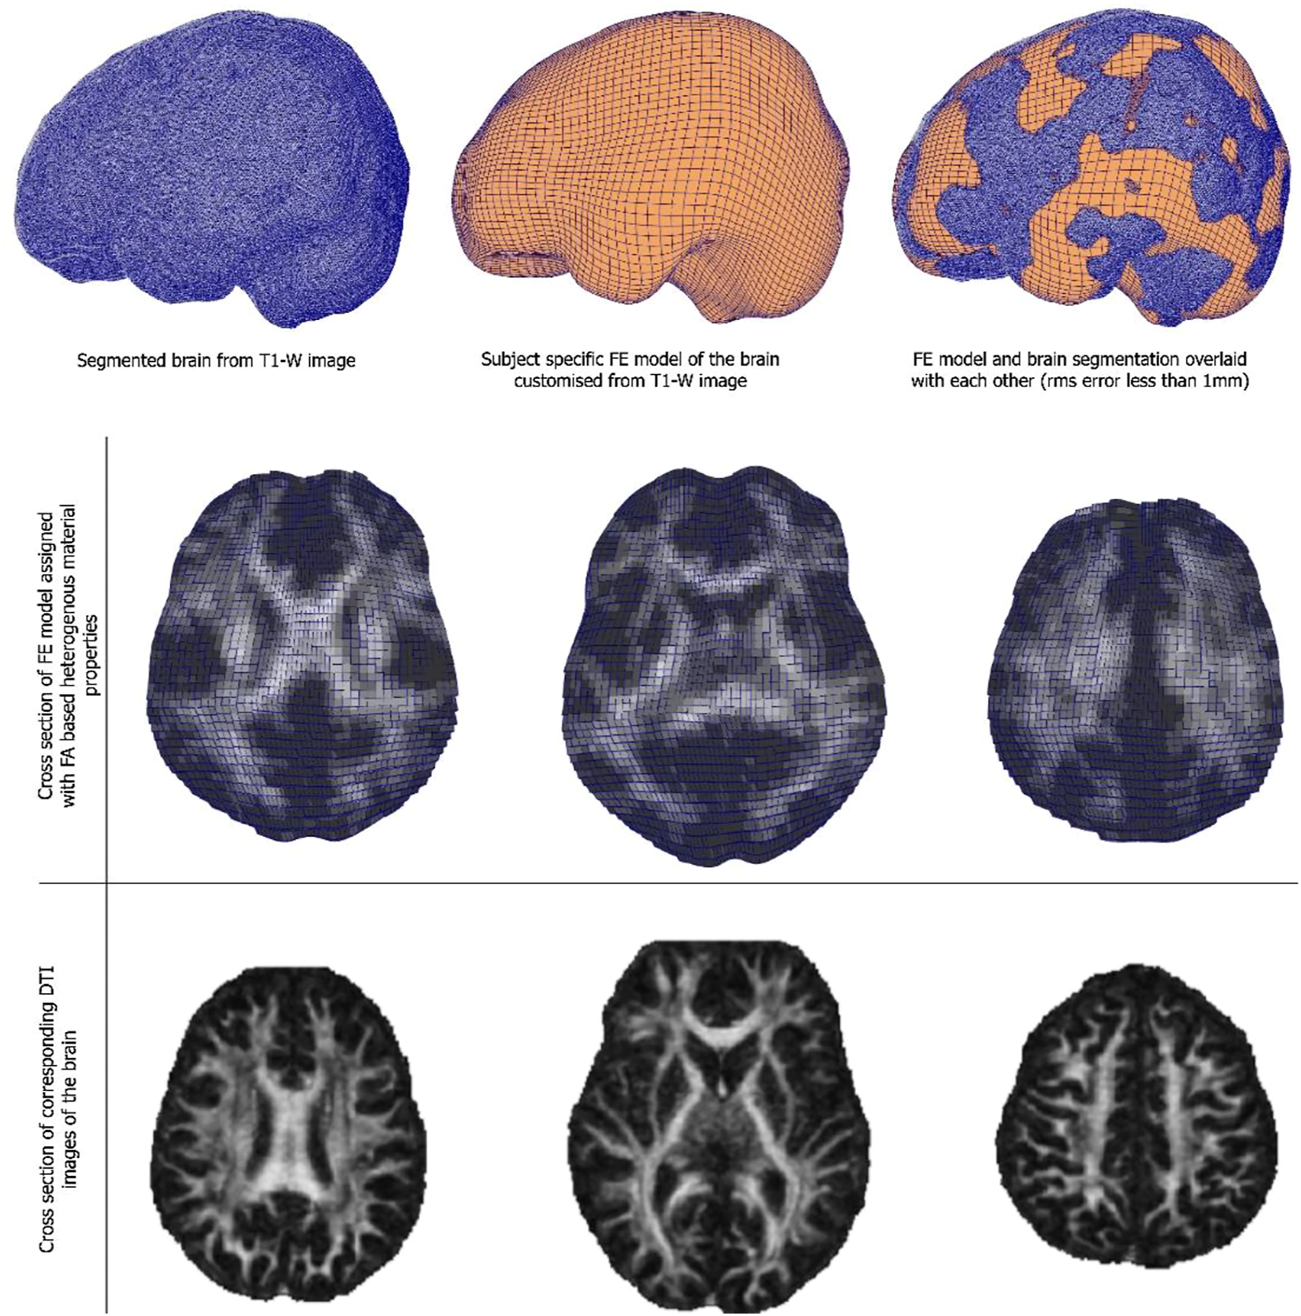

3.3 Child-specific brain model results

Customised brain model results are shown in Figure 3. The model customization to the segmented brain image was performed with the accuracy of less than 1 mm RMS error between the model and the segmented images. Figure 3 shows the material property assignment using the FA values of the DTI images. It demonstrates how the model captures subject-specific heterogeneous anisotropy of the brain.

FIGURE 3

(Top and middle row) An exemplar case of child-specific brain model customized to an anatomical T1-weighted image and FE model overlaid. (Bottom row) Cross section of the diffusion tractography (DTI) images with FA-based heterogeneous material properties.